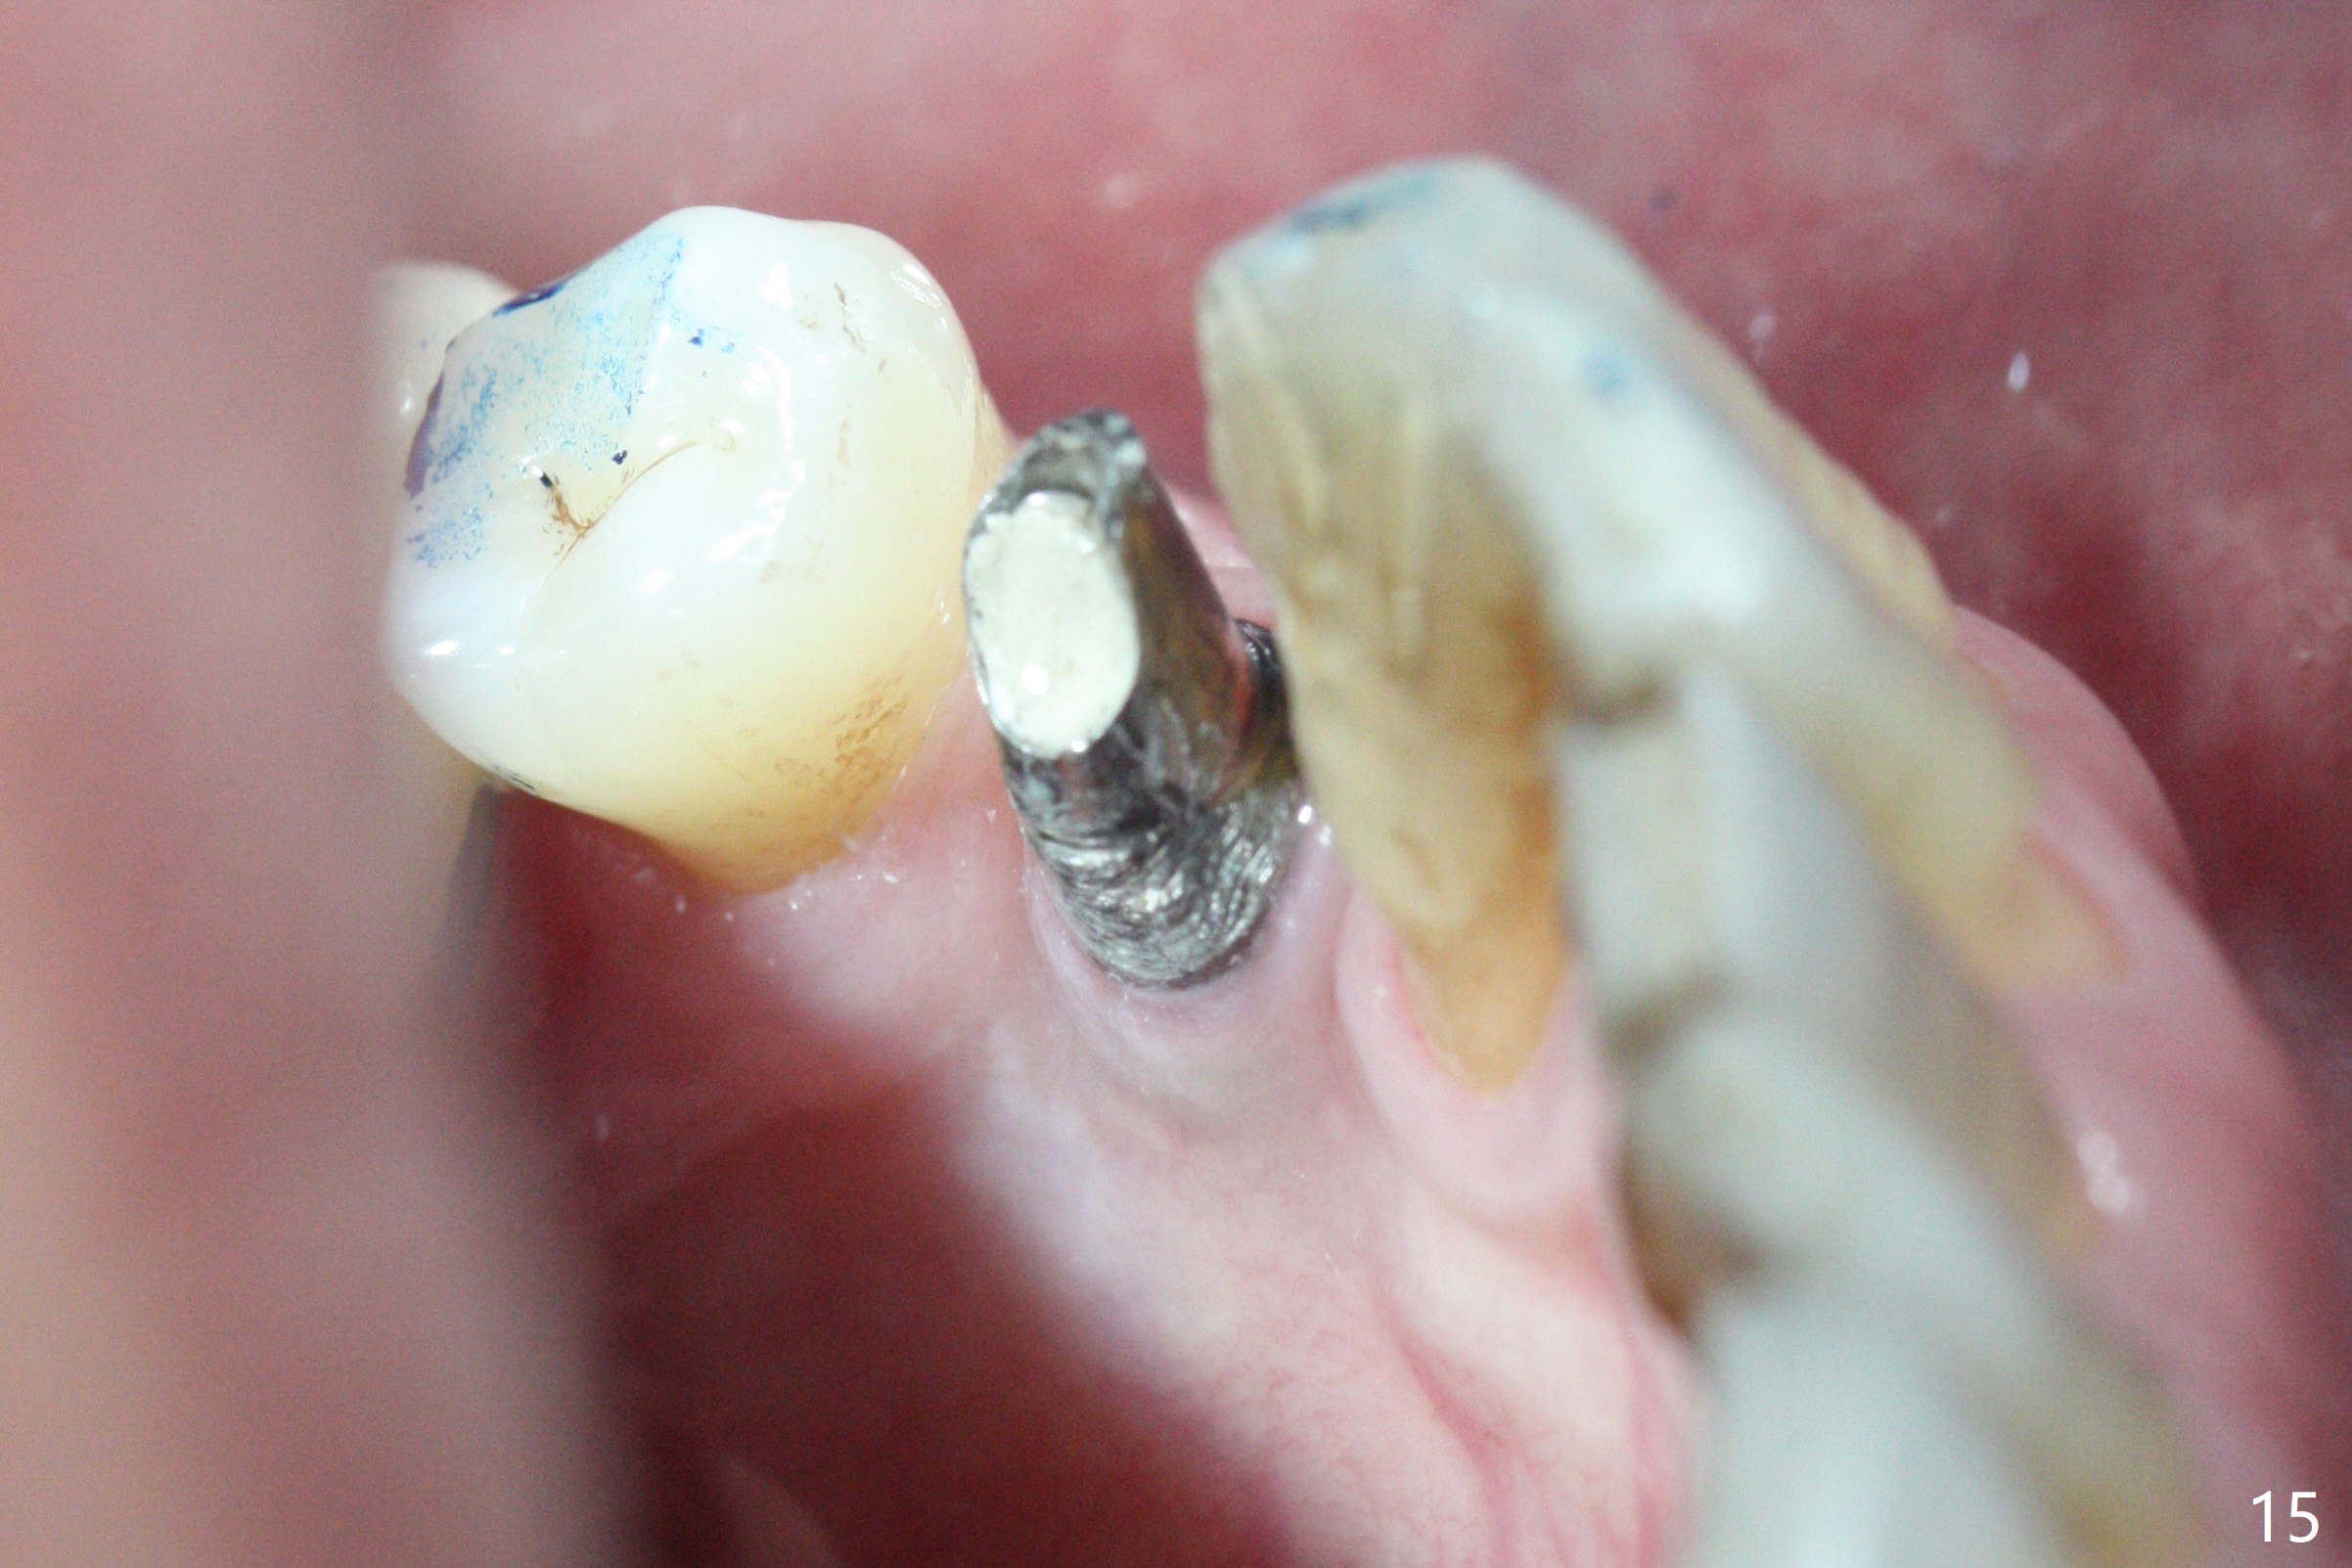

The residual root at #21 seems to be buccally positioned (Fig.1 *). The initial osteotomy is established with the 1.6 mm drill at 11 mm (Fig.2). Later the depth increases to 13 mm. The initial osteotomy is found to be too lingual, but experience shows that as osteotomy increases in diameter, the trajectory would shift buccally due to the thick lingual plate (slope). When 3.3 mm Magic drill reaches 11 mm, the patient feels pain. It is probably due to the dense bone. A 4x11 mm IBS implant cannot be seated due to high torque; it is removed. The osteotomy is increased with 3.8 mm drill. The implant is re-seated with >55 Ncm; it is over-lingually placed. Due to failure to seat the implant driver completely, the implant cannot be un-torqued. A 4.5 mm 15° angled abutment (3 mm cuff) is placed for immediate provisional (Fig.3,4 *).